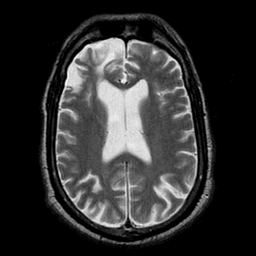

Subacute Stroke overlay -- Slice #14

[Home][Help][Clinical] Slice 14